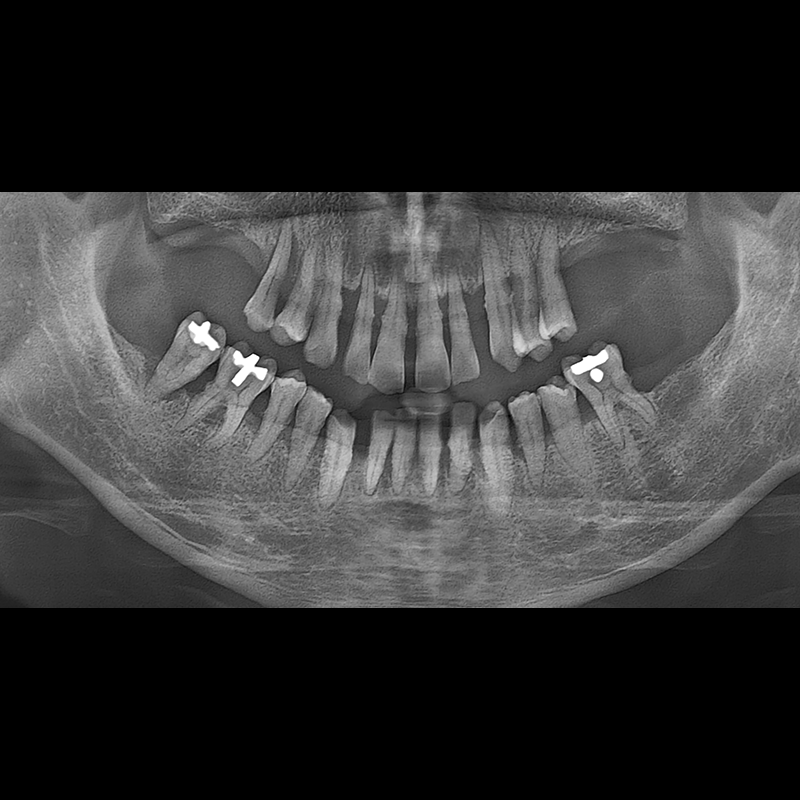

BEFORE AFTER

种植牙前后的照片 2025.05.30

在缺失的牙齿部分和难以挽救的牙齿位置植入了种植牙。